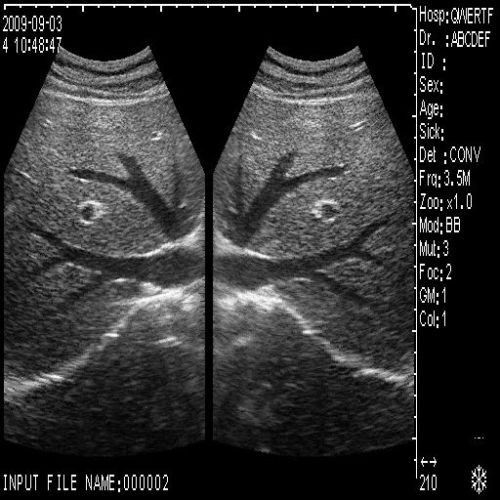

image: +3D High clear

Probe Function: 3.5MHZ convex, abdominal organs

The new Ultrasound Scanner introduces groundbreaking 3D dynamic imaging technology, allowing for real-time visualization. This means that healthcare professionals can capture and analyze images as they happen, providing immediate information for diagnoses. Utilizing dual probes—convex and transvaginal—this device offers flexibility and precision, enhancing its usability in various medical settings. The advanced imaging helps doctors to examine structures and functions with clarity, making the diagnosis process more efficient.